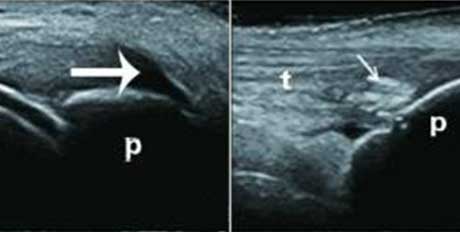

��������Ӱ

ϥ�ؽ����������Ż�Һ���ɼ���״ǿ������������Ӱ

������

�ؽں���ɨ��ͼ�������γ����γ��Ը����ſ�-ʹ��ʯ